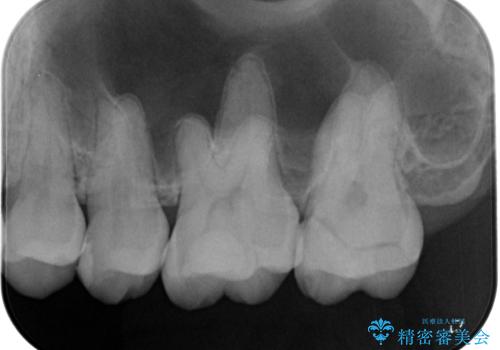

レントゲン上で詰め物とご自身の歯の間に隙間を認めました。

拡大鏡視野下で詰め物と虫歯の除去を行い、詰め物の範囲が大きかったためオールセラミッククラウンに適した形に整えました。